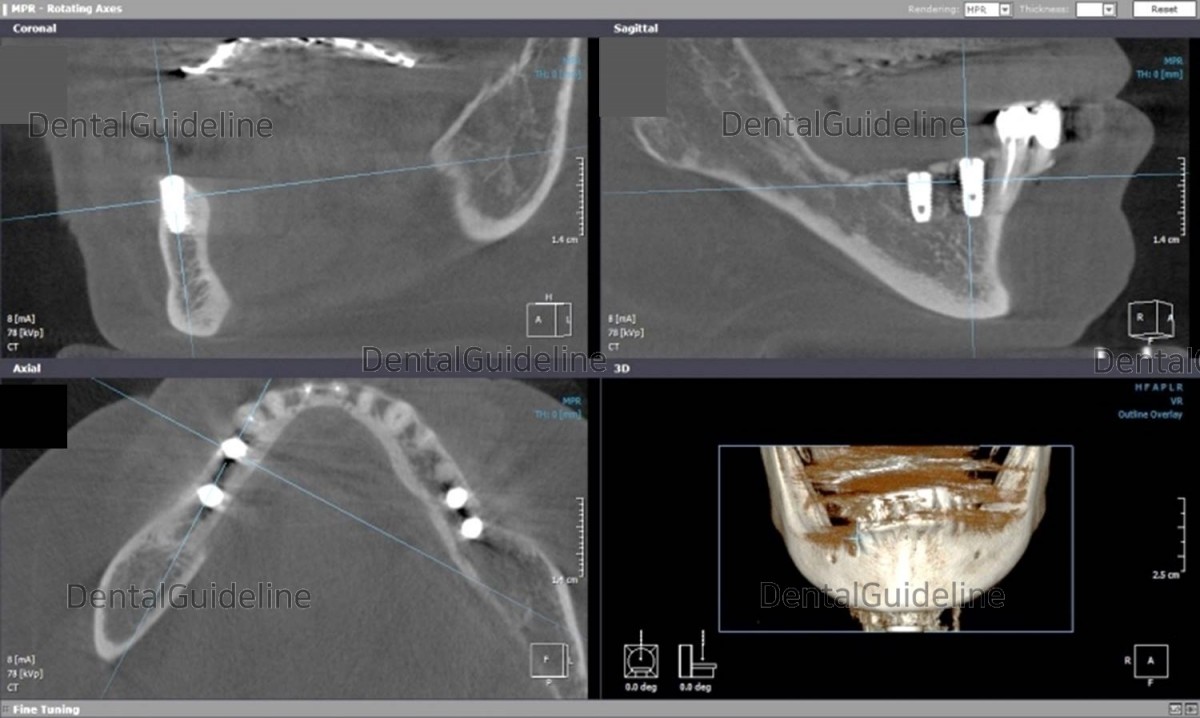

CBCT

after 1 month of implant surgery.![]()

CBCT after 1 month of implant

surgery. The lateral alveolar bone of the implant is thin.

As expected from CBCT, the

remaining alveolar bone on the outside was thin.